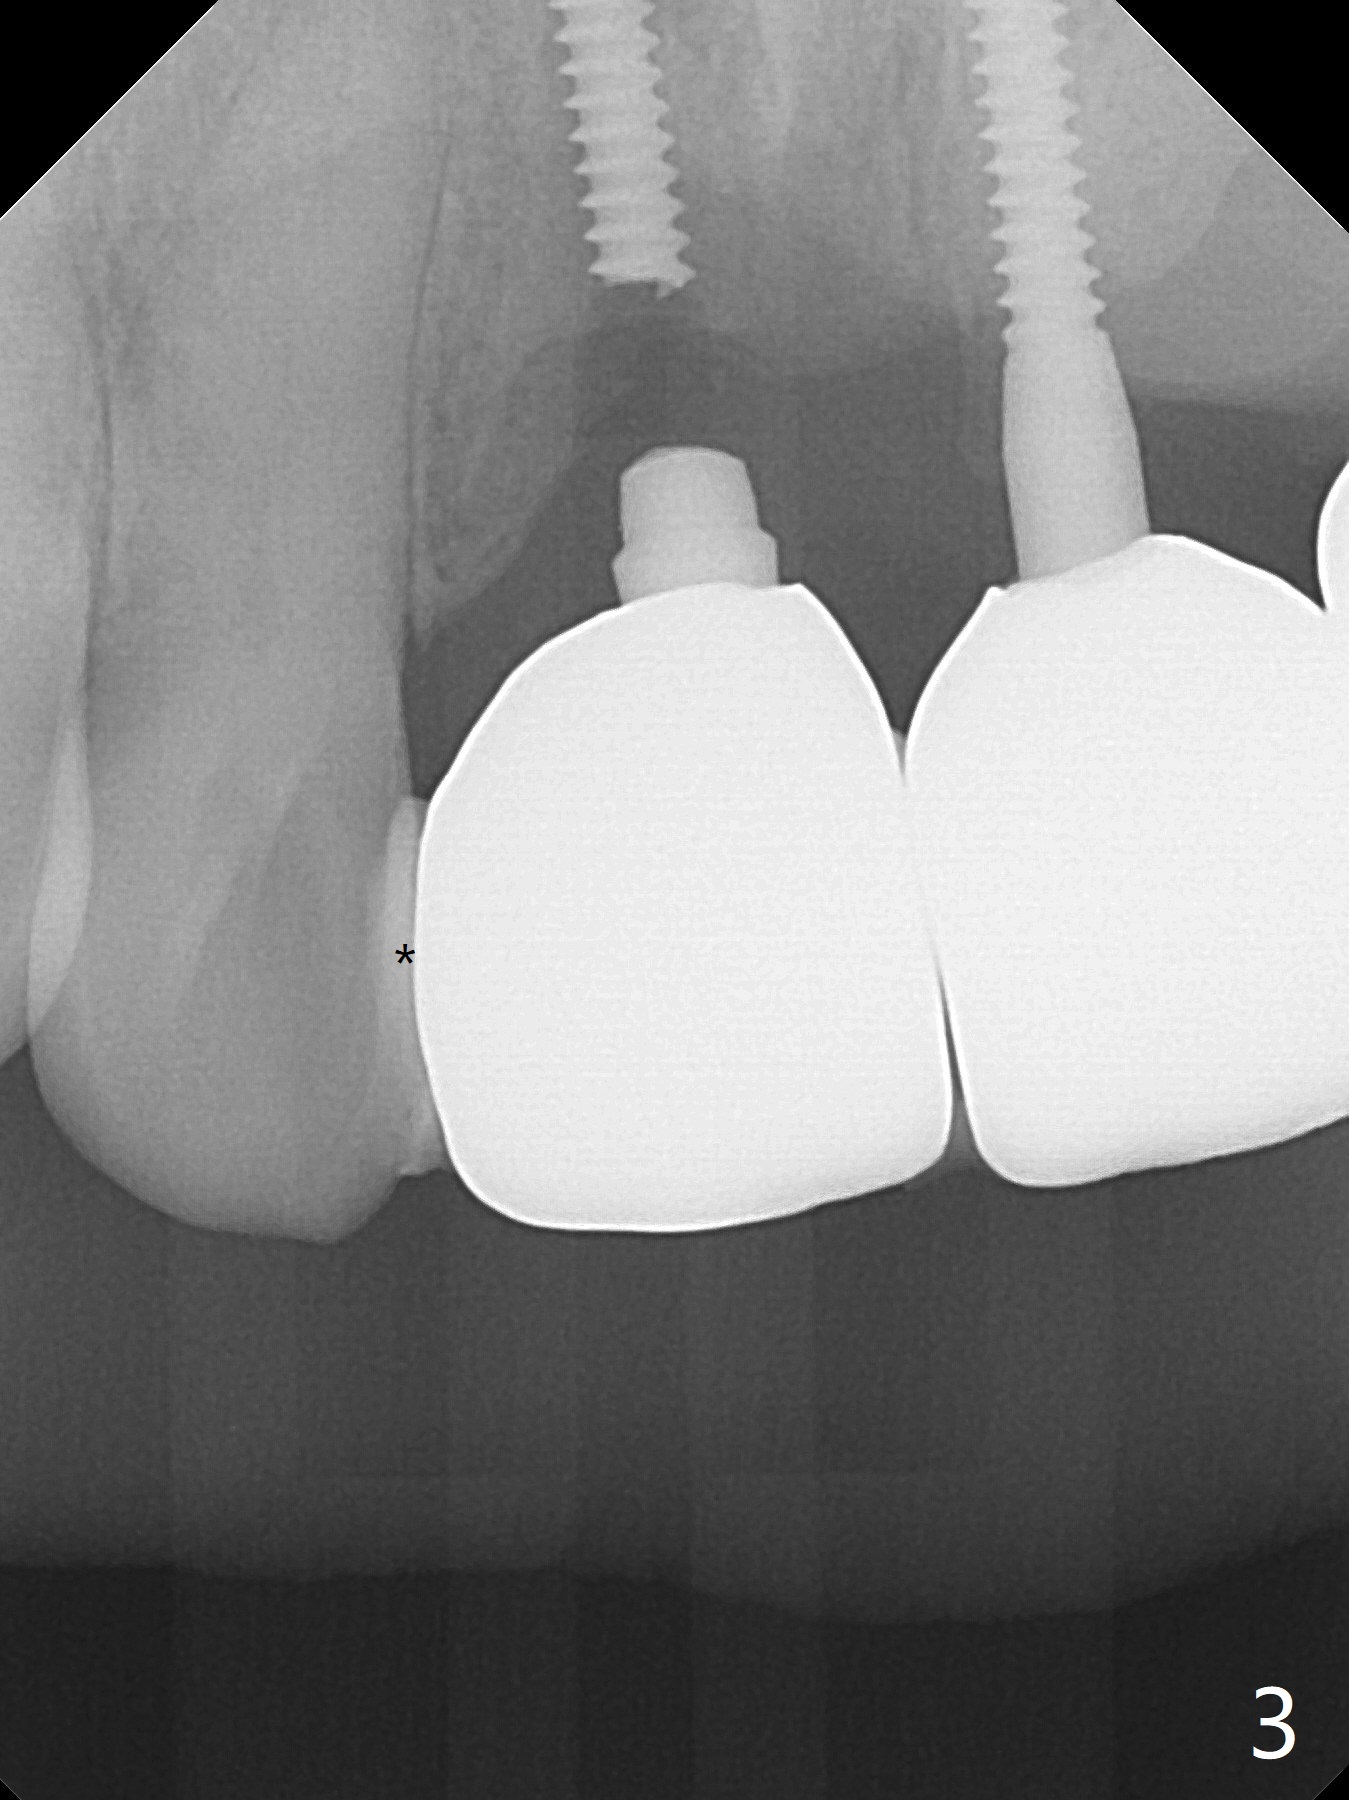

A 43-year-old man has 6 of 1-piece implants in the maxilla (#8-13). His daughter's head hits his upper anterior teeth 7 months post cementation. Exam shows that the tooth #7 has mild percussion. Nine months later the implant crown at #8 becomes displaced and loose when he bites apple (Fig.1 arrow). Forceps are used to remove the crown, leaving a concave implant site (Fig.2). After the crown is bonded to the neighboring tooth/implant crown (Fig.3 *), the patient feels pain from the neighboring tooth. The alveolus is 4.3 mm wide (Fig.4 (2.9 mm preop)), allowing 2.5 or 3.0 mm immediate implant re-placement (Fig.5). A 2.0/3.0 mm trephine bur will be used for implant removal. Try to place the new implant slightly distal to improve the trajectory (Fig.6). Particulate and/or onlay graft is an option. Prepare dummy implants. As planned, the fractured implant is removed by using a 2.0/3.0 mm trephine bur following incision (Fig.7). After use of Lindamann bur to remove the distal bone, a 3x14(4) mm dummy implant is placed with 20 Ncm (Fig.8). A longer implant could be used (3x16(2 or 4) mm), but a 3.5x13 mm 1-piece implant is placed with ~ 50 Ncm after use 3.0 mm drill (Fig.9,10). Allograft is placed around the implant (Fig.9,10 *), followed by Amnion-Chorion membrane and 5-0 PGA sutures (Fig.11). Allograft placed around the implant (Fig.9 *) appears to be able to prevent implant thread exposure 4 months postop (Fig.12). PA is taken when the crown is cemented (Fig.13). Four months postop cementation of #8 crown, the patient returns because of #9 mobility (Fig.14). In fact the implant fractures when the loose crown is removed with forceps; there is bone loss at #10. Bone graft will be placed at #10 with sticky bone (PRFx1), while the implant at #9 is redo. The ridge is wide enough for a 3.5x10 mm implant (Fig.16 (CT taken when #8 implant fractured)). Also prepare Tatum angled 1-piece implant. The 2 mm implant is too thin when occlusion contact at #10-13 is incomplete. The crowns will be redone when the implant at #9 is osteointegrated.